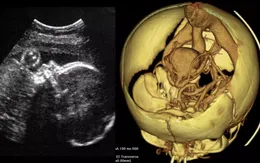

Ca phẫu thuật não đầu tiên trên thai nhi trong bụng mẹ được thực hiện

VTV.vn - Các bác sĩ lần đầu tiên thực hiện ca phẫu thuật não của một bào thai trong bụng mẹ để chữa mạch máu bị dị dạng.

13/05/2023